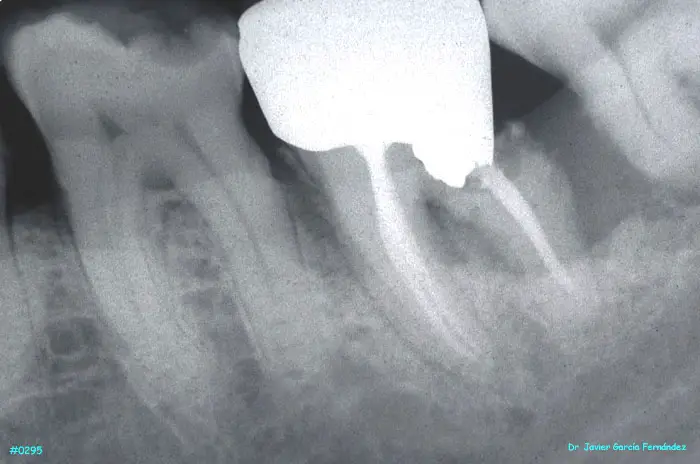

ATLAS DE CIRUGIA PERIODONTAL